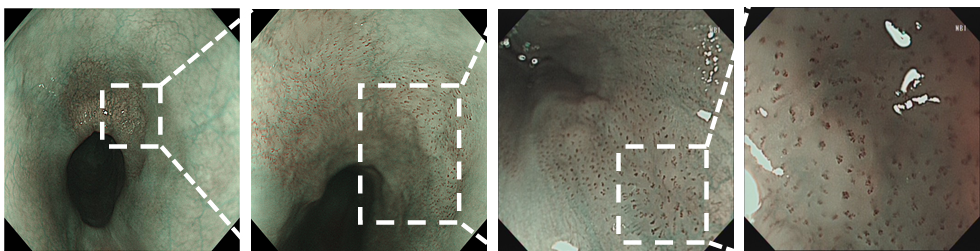

肛侧端IPCL仍然相对比较稀疏,呈B1改变,同样形成玫瑰花环样结构。

年轻女性,既往有饮酒史。结合白光内镜提示Ⅱb型色泽发红病变,碘液喷酒后病变区域淡染色,稍吸气可见“榻榻米”征。M-NBI呈褐色区域,放大内镜下IPCL稀疏,局部有拉长、扩张及扭曲,呈不典型B1改变,局部仍然可见典型的IPCL呈B1改变,病理提示鳞状上皮高级别上皮内瘤变,术前诊断食管早期癌,浸润深度考虑为M1-M2,属于内镜下治疗的绝对适应证,患者进一步行ESD治疗。